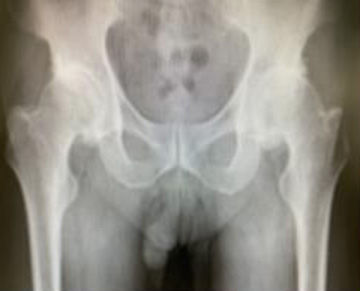

• 手術前